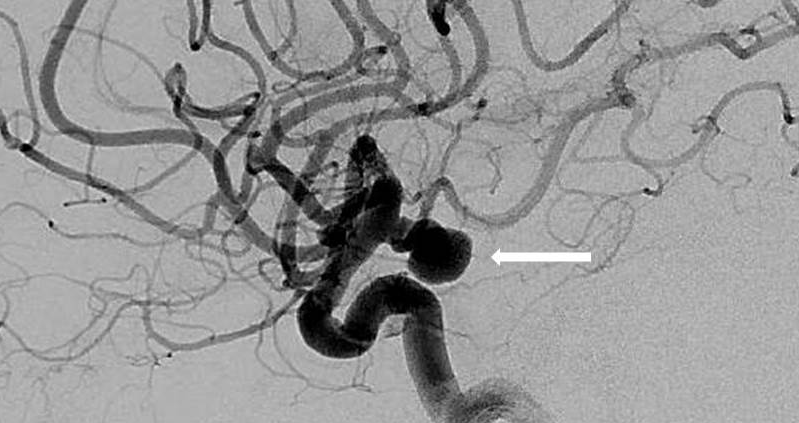

A brain aneurysm is a balloon-like bulge in the blood vessel wall and it is caused by a weakening of the artery’s walls that causes them to slowly stretch and grow over time. Aneurysms pose danger because as they slowly expand, they can rupture leading to blood exiting the vessel through a tear in the aneurysm and bleeding into the fluid space around the brain. Read more…